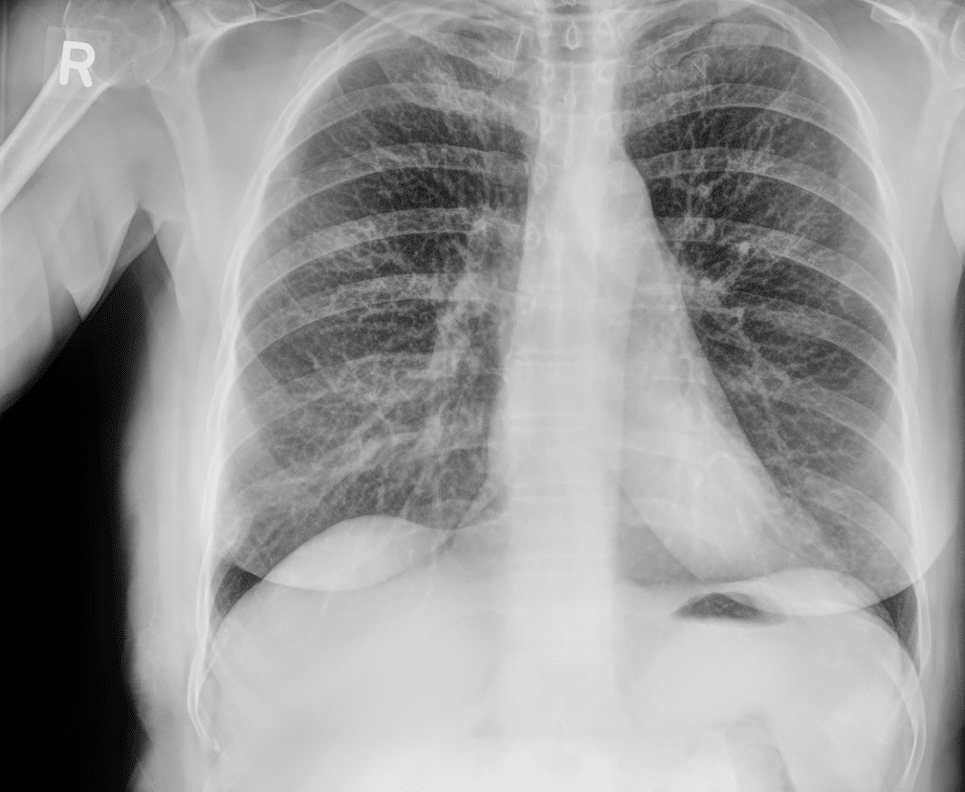

Pneumothorax Evaluation

Soft-tissue images reduce rib overlap and may improve visualization of pneumothorax in trauma patients.